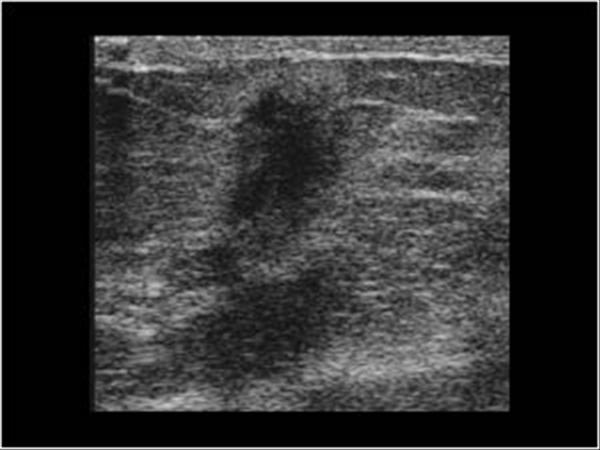

Ung thư vú

Ung thư vú - Ảnh 2

» Thông tin: Nữ giới – 59 tuổi.

» Lâm sàng: Khối tuyến vú.